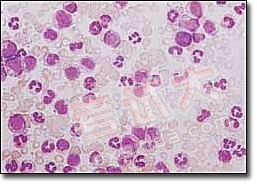

1.周圍血象 主要為白細胞增多,80%在100×109/L以上。血色素在80g/L左右。血小板增多。分類可見粒系增多,包括嗜酸、嗜鹼粒細胞增多。原始粒細胞增多不明顯,以中、晚幼和成熟粒細胞為主。

3.骨髓檢查 增生活躍,以粒系增生為主,原始粒細胞<10%,多為中晚幼粒細胞及桿狀核細胞粒∶紅為10~50∶1。部分患者可見骨髓纖維化。骨髓巨核細胞明顯增多,以成熟巨核細胞為主。骨髓培養集落與叢落皆增多